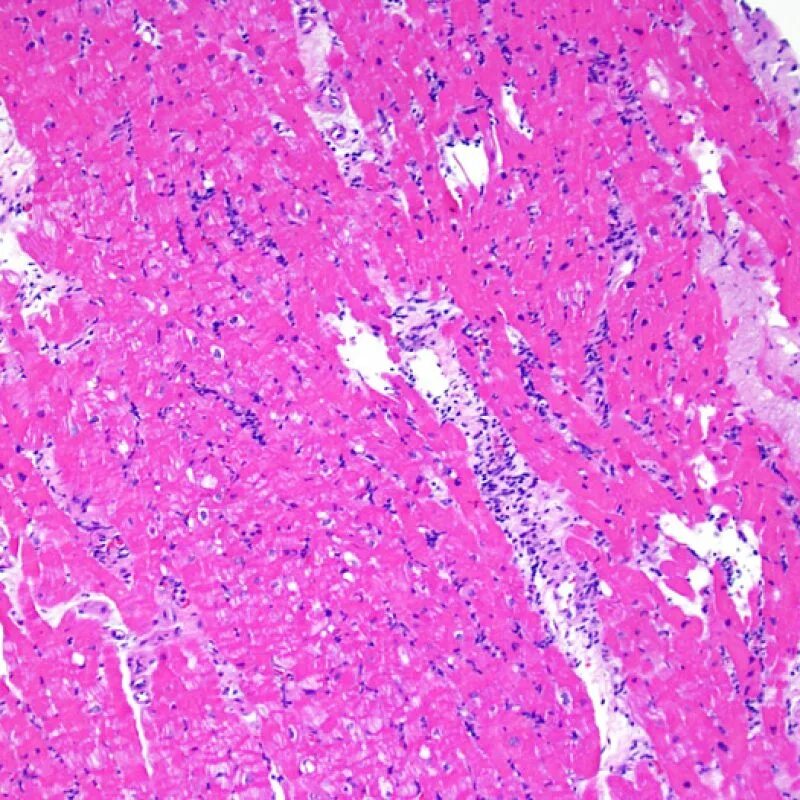

Смешанный периваскулярный инфильтрат при крапивнице